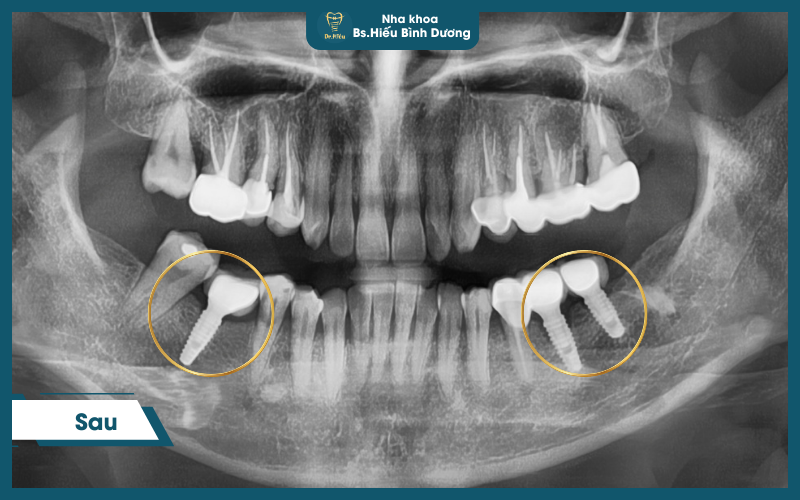

Quy trình chuẩn y khoa

- Thăm khám & chẩn đoán toàn diện bằng CT Cone Beam 3D

- Lập kế hoạch điều trị chính xác

- Cấy trụ Implant trong môi trường vô trùng

- Chờ tích hợp xương 1-3 tháng

- Phục hình răng sứ đúng khớp cắn

- Theo dõi & bảo trì định kỳ 6 tháng/lần